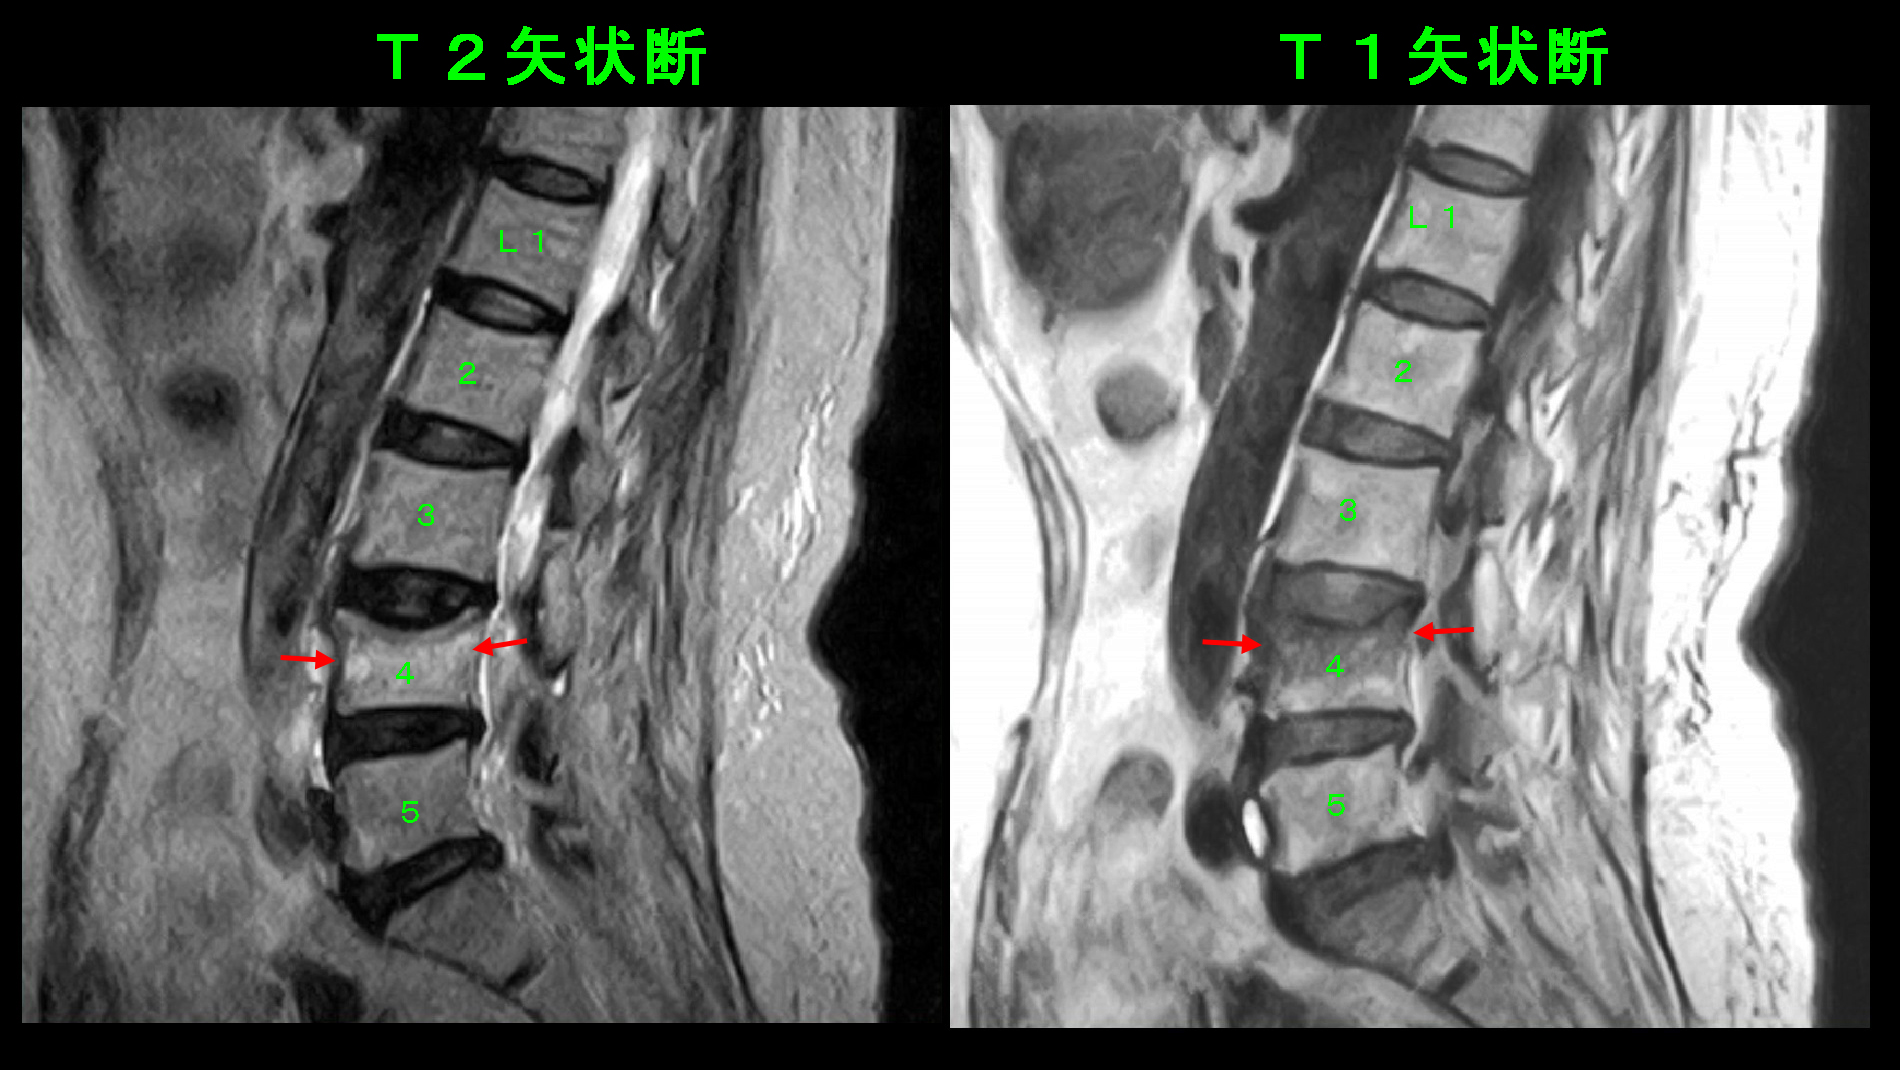

71才女 MRI1.jpg

腰椎MRI検査では、左のT2矢状断(側面像)ではL4は若干高輝度(白っぽくなっている)、右のT1矢状断ではL4は上半分が低輝度(黒っぽくなっている)であり、これはL4が損傷を起こしている(=圧迫骨折を起こしている)状態を示しています。この状態で作業労働をすることは無理であり、2か月の休職の診断書を記載し、安静と服薬(骨粗鬆症治療薬と鎮痛剤)で治療を開始しました。Nさんは2か月経過して日常生活ではほぼ支障がなくなったのですが、仕事を再開するとまたあの痛みに襲われるのではないかという不安感を払しょくできない様子でした。しかし、4月1日から昼食分だけでの勤務を再開され、令和3年5月まで勤務されました。